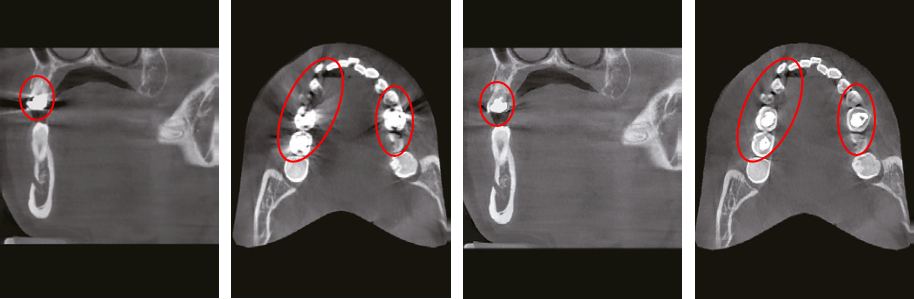

Practitioners want to diagnose with a CBCT that doesn’t get affected by metal artifacts and while still producing high 3D image quality. SMART MAR provides this powerful capability to its users.